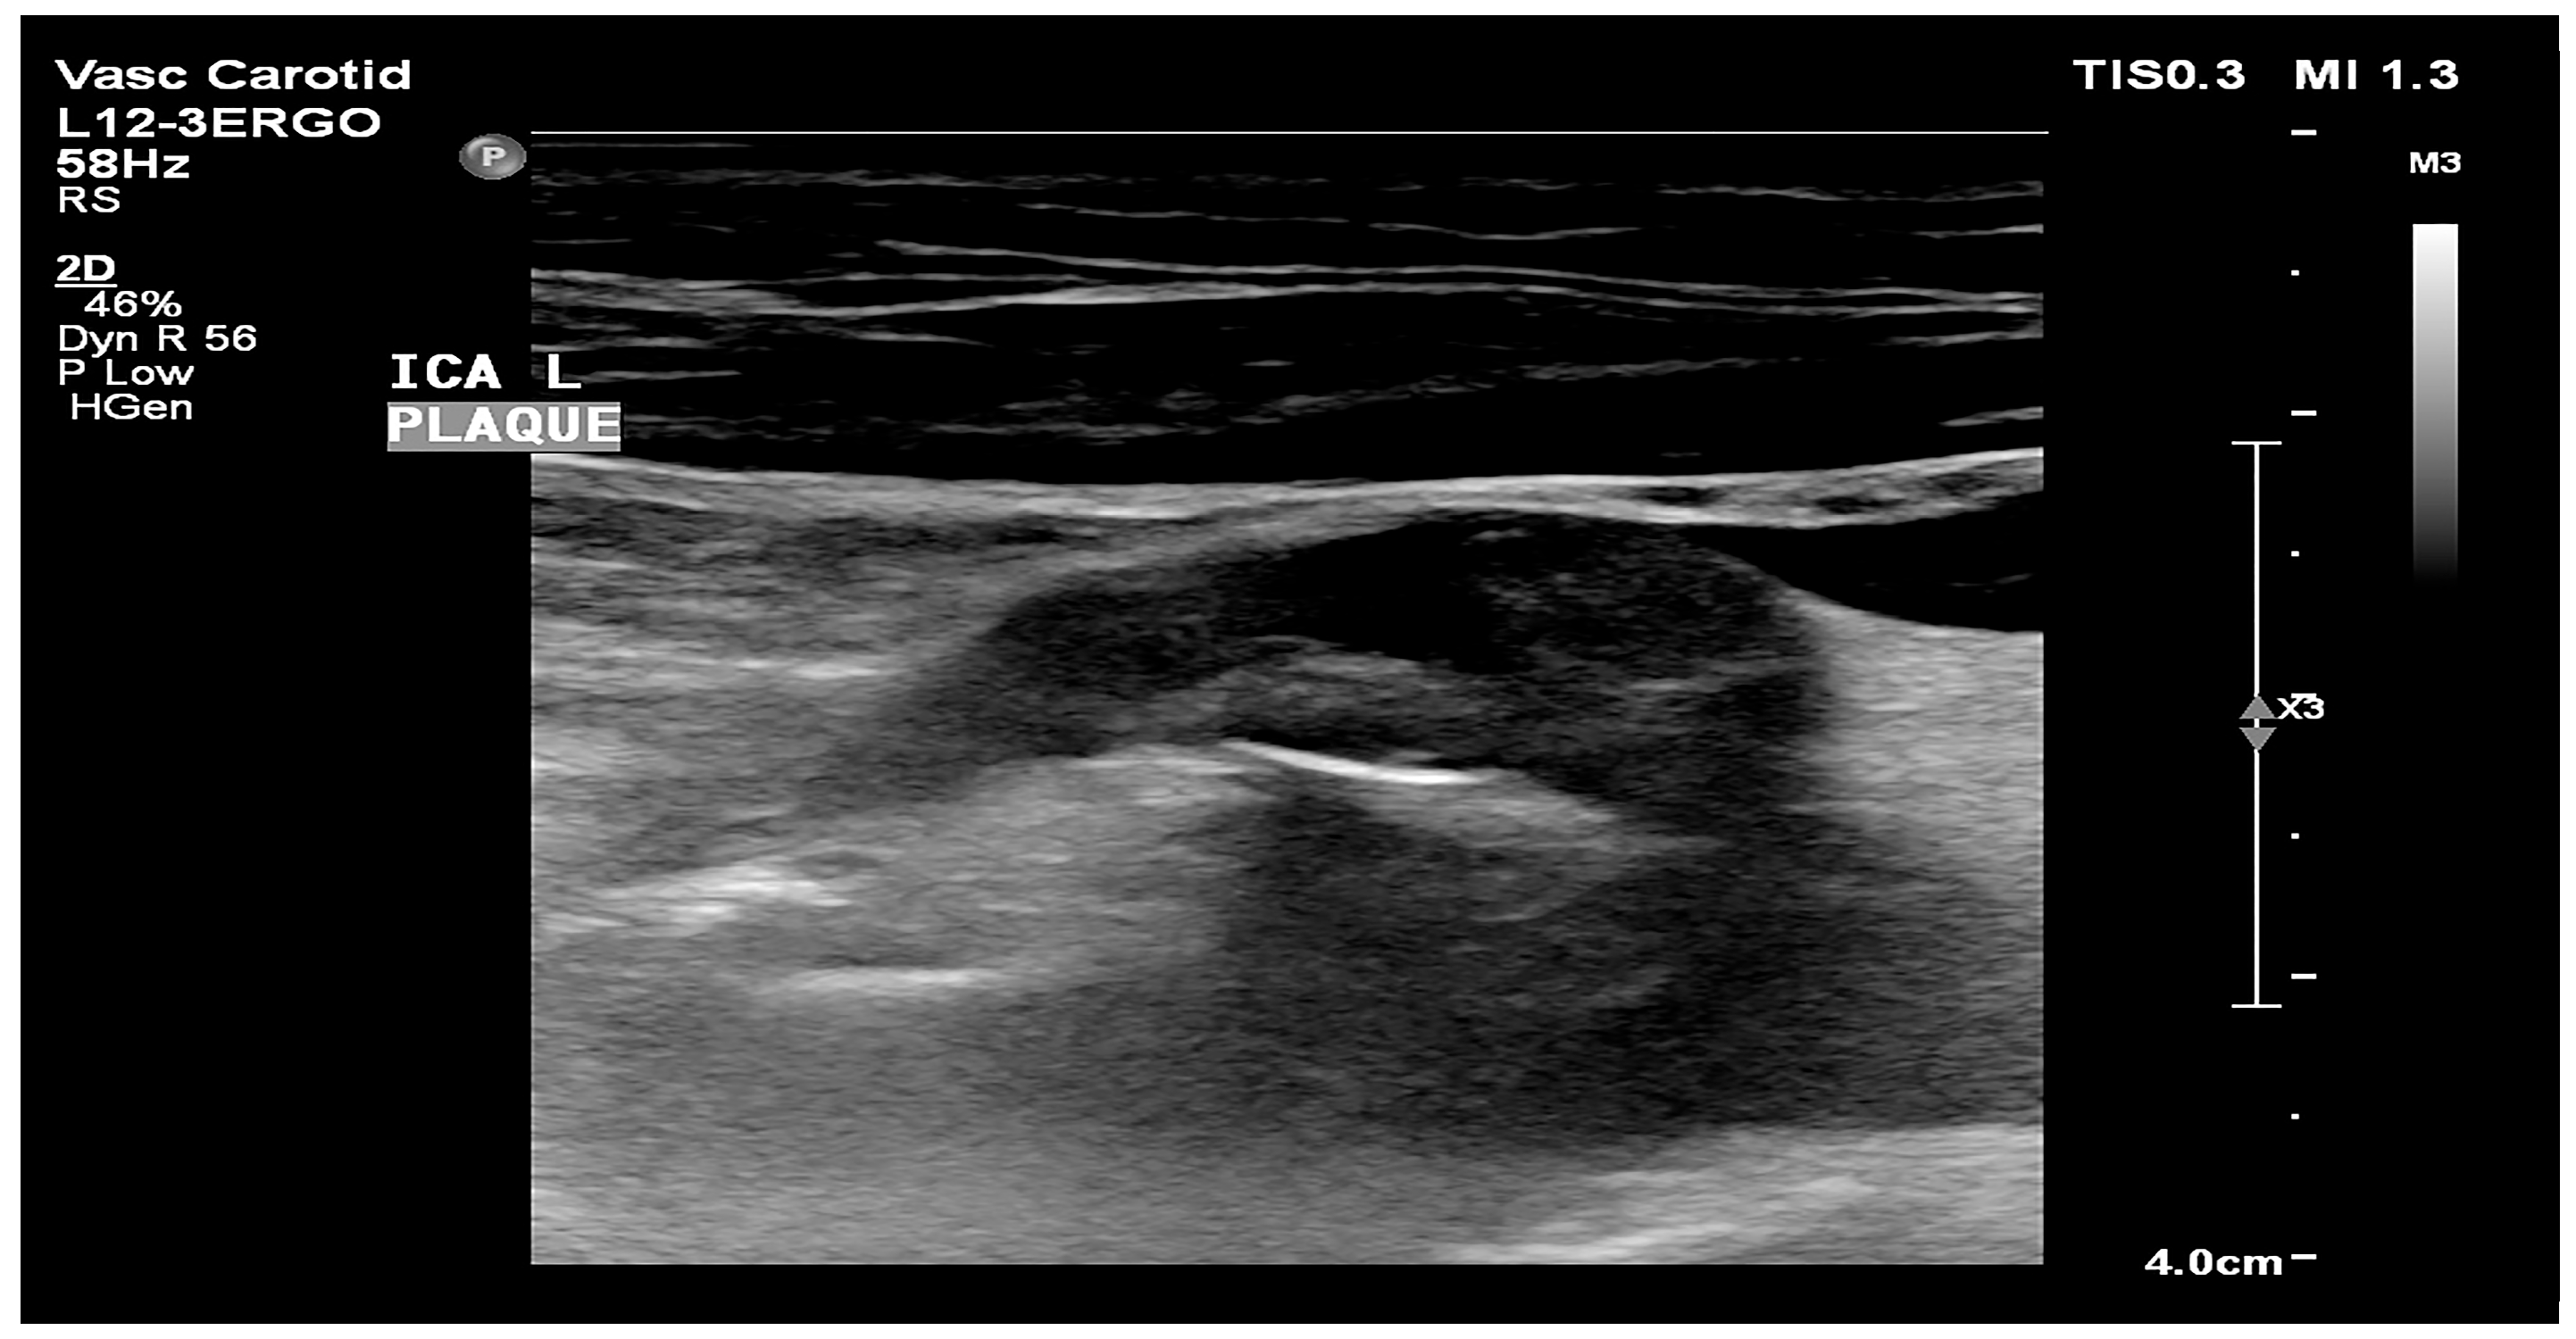

- Atherosclerotic plaque—during the ultrasound examination, the best possible image projection in B-mode presentation was selected with the entire atherosclerotic plaque visible—the image was not enlarged or brightened—according to the accepted standardization. The image of the plaque was recorded on a photograph. Then, to assess the atherosclerotic plaque, images from the ultrasound examination were used to analyze its structure on the GSM scale.

- Images of the visible atherosclerotic plaque in the carotid artery.